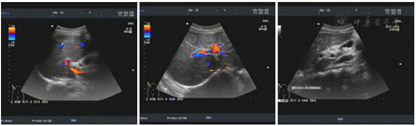

完善血常规、自身免疫肝病抗体检测、ANCA+狼疮全套、肝功能、风湿免疫全套、腹部彩超、肺部CT等检查,诊断为系统性红斑狼疮、自身免疫性肝炎、肝功能不全。

结合临床,该患者诊断为:(1)系统性红斑狼疮;(2)自身免疫性肝炎、肝功能不全;(3)全血细胞减少;(4)右中肺胸膜结节(性质待定)、右下肺结节钙化灶(性质待定)、右下肺少许炎症;(5)甲状腺功能减退。

患者转入我科后,进一步查骨髓细胞学及活检未见明显异常,尿培养阳性提示泌尿系感染,PPD皮试(2+),T-spot阳性,肺部CT有结节、钙化病灶(性质待定),怀疑有结核可能。给予抗感染、护肝降酶等治疗的同时,需积极排查结核,激素、免疫抑制剂治疗暂缓,给予血小板生成素(TPO)升血小板治疗,病情明确、感染控制后予足量激素抗SLE,患者病情好转出院。